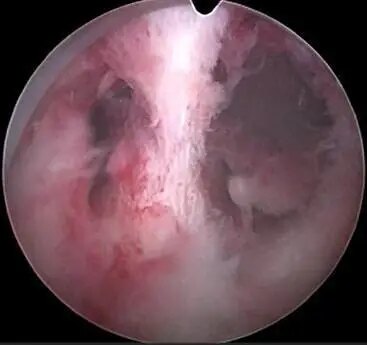

2.子宫腔感染:各种细菌病毒支原体衣原体等引起的宫腔内感染会使得子宫内膜表面的各种炎性因子增加,炎性渗出物增加,导致宫腔积液。

3.宫腔黏连:也常见到重度宫腔黏连的患者宫腔镜粘连分解术后内膜准备移植时发现宫腔内积液了!这是因为黏连的子宫内膜往往合并感染加之大量的雌激素内膜分泌物多,同时黏连的内膜重吸收代谢的能力下降,宫腔容易积液。

无法确定输卵管有积液又不能贸然腹腔镜手术时可以先尝试宫腔镜检查,也可以发现很多问题,比如子宫内膜炎症,内膜黏连,还有剖腹产切口的憩室大小等。针对不同的问题给与相应治疗,比如抗炎、黏连分解、和憩室修补等。